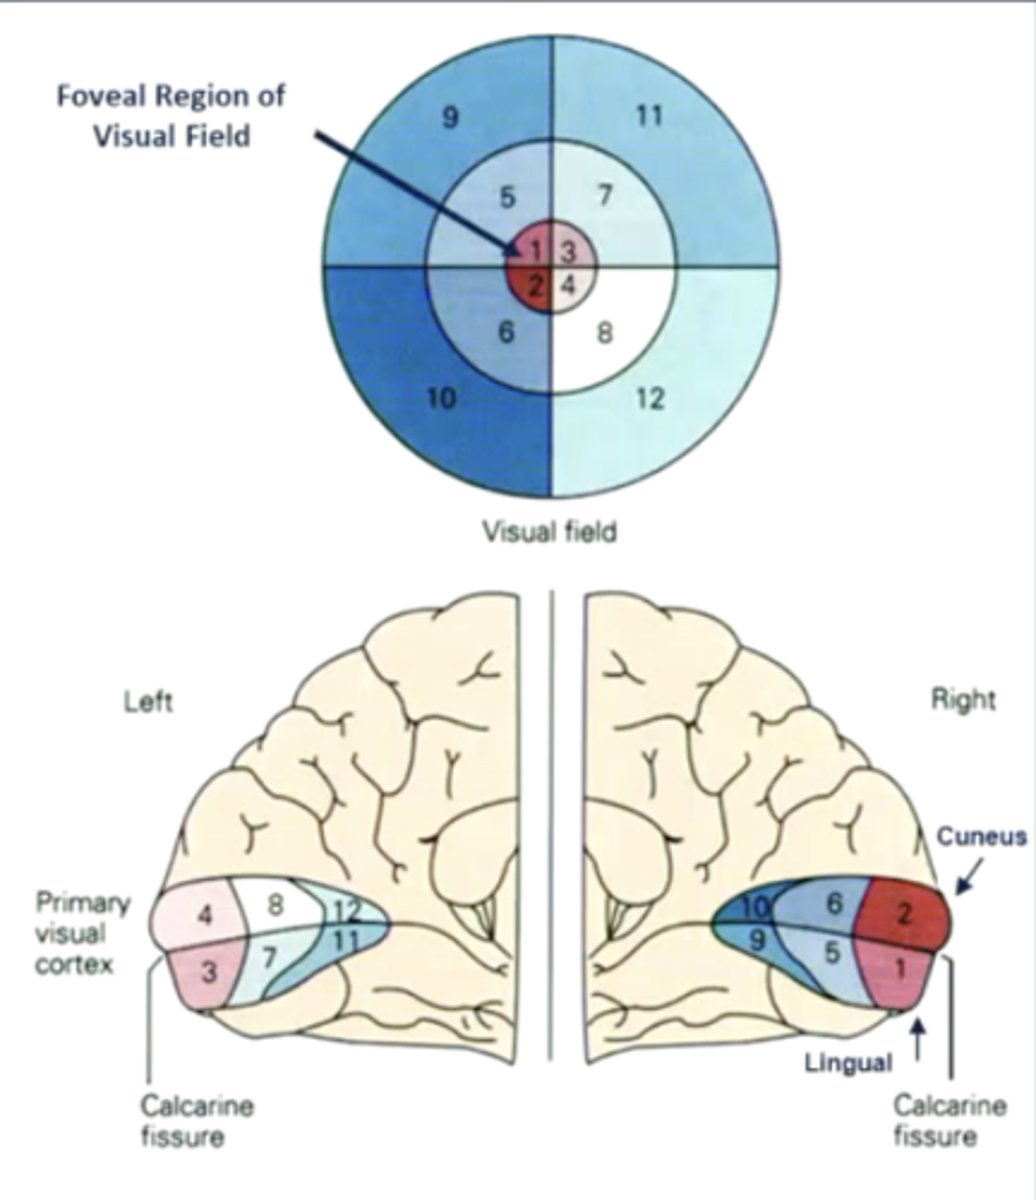

list the cortical region and cerebral lobe of the visual system:

cortical region:

calcarine sulcus

cerebral lobe: occipital (V1)

what are the 2 "rules" of the primary visual cortex?

1. retinotopic organization (contralateral visual fields)

2. increased cortical surface area = increased receptor density/visual acuity